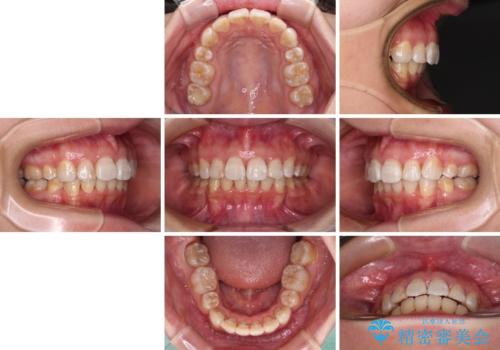

飛び出した前歯を引っ込めたい 目立たないワイヤーでの抜歯矯正

- 口元の閉じにくさと、前歯のでこぼこの歯並びを気にして来院された患者様です。

口元を積極的に引っ込めるために、上下左右の小臼歯計4本を抜歯することとしました。

咬み合わせが深く、咬合力強いため、補助装置を使用しながら積極的に口元を下げることとしました。

矯正治療終了近くに九州へ引っ越すことになってしまい、なかなか来院することができなくなったため、引っ越してから1年以上の期間が必要となってしまいました。